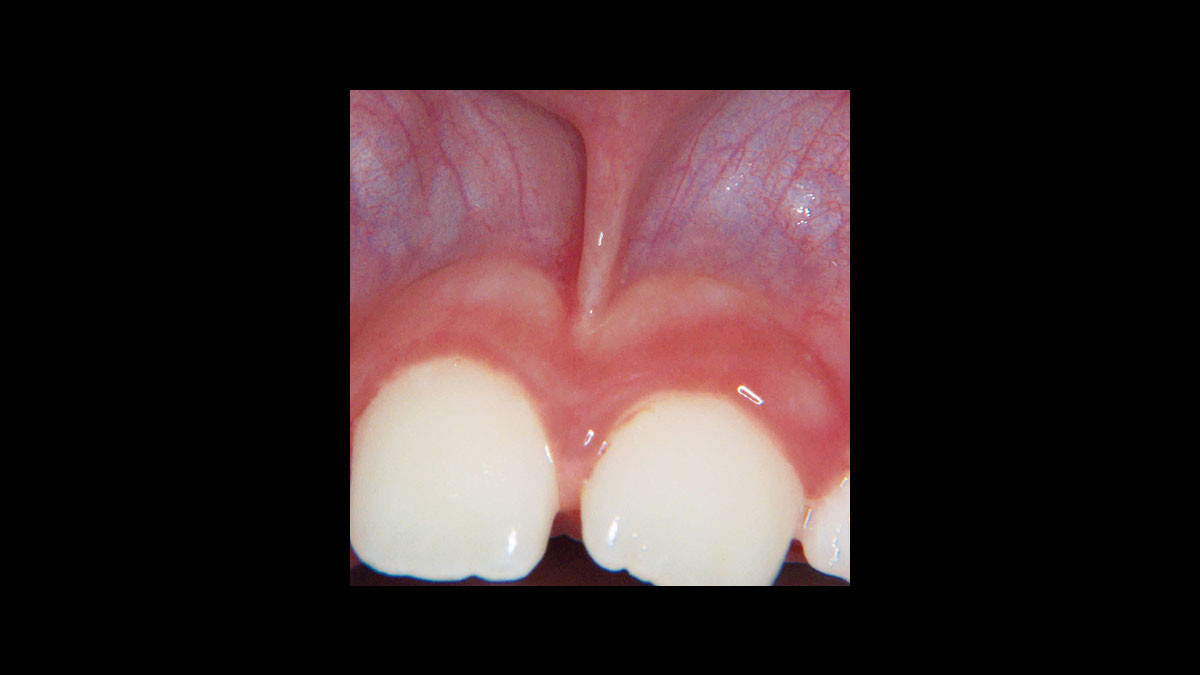

Fibroma

Frenectomía

Gingivoplastia